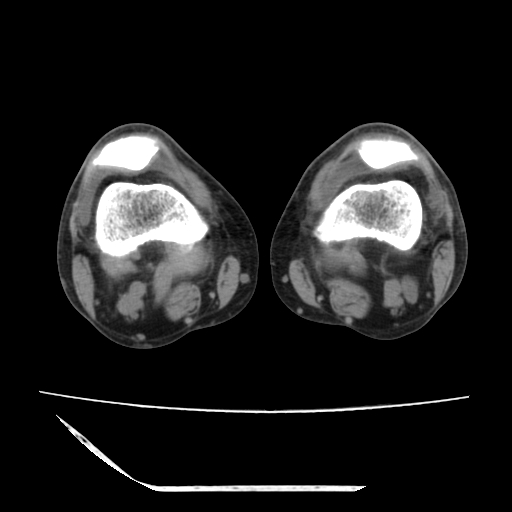

标题: CT13225:老年男性,左膝关节疼痛数月;请各位老师讨论。 [打印本页]

标题: CT13225:老年男性,左膝关节疼痛数月;请各位老师讨论。

骨质增生,骨性关节面硬化,关节积液,考虑退行性骨关节病

关节腔内少量积液,关节面退变。

双膝退变

骨质增生,骨性关节面硬化,关节间隙失常,关节积液,考虑退行性骨关节病.

骨质增生,骨性关节面硬化,关节积液,考虑退行性骨关节病。

这个病例诊断:退行性骨关节炎